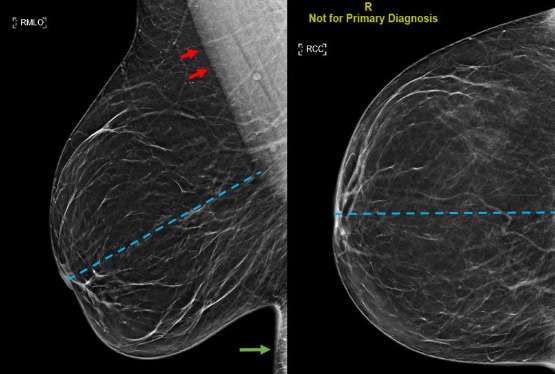

The posterior nipple line

Figure 1: Technically adequate mediolateral oblique view of the right breast (left). The pectoralis muscle (red arrows) appears straight. The PNL (blue line) intersects the pectoralis muscle perpendicularly. The inframammary fold (green arrow) is included

Mediolateral Oblique (MLO) View

A good mediolateral oblique (MLO) view provides visualization of the greatest amount of breast tissue, including the posterior breast and axillary region (Figure 1). When obtaining an MLO image, the breast is placed on the image receptor which lies parallel to the pectoralis muscle. The compression paddle then compresses the breast from a superomedial direction. In order to determine whether acquisition technique is adequate, it is important to assess three factors: the presence and position of pectoralis muscle, the posterior nipple line (PNL), and the inframammary fold.3

Ideally the margins of the pectoralis muscle appear as straight lines or convex curves, which implies breast tissue has been sufficiently pulled forward. The posterior nipple line should be able to intersect the pectoralis muscle at a perpendicular angle. The inframammary fold (IMF) is the most inferior portion of the breast which intersects the chest wall and should be included in the MLO image. Inclusion of the IMF promotes detection of masses that may be located in this most inferior aspect of the breast.